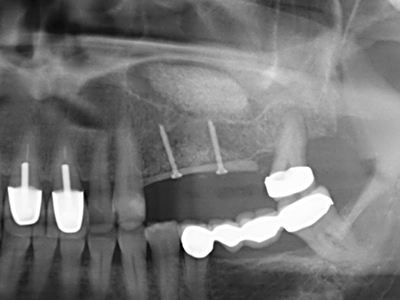

Fig. 11: la panoramica postoperatoria mostra l'accrescimento verticale e il rialzo del pavimento sinusale.

Fig. 12: dopo sei mesi di processo di guarigione, la cresta alveolare è vitale e sufficientemente dimensionata in tutti i piani.